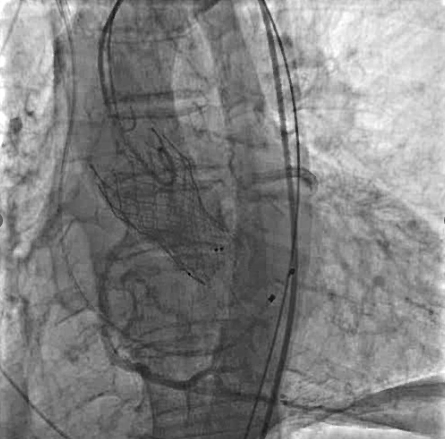

冠脉造影及介入治疗:将ACIST CVi血管造影注射系统调整至冠脉造影模式,完善冠脉造影。结果示:LM未见明显狭窄,LAD近端80%狭窄,严重钙化,IVUS可见360°钙化。回旋支少量斑块浸润,右冠状动脉30-40%狭窄。决定处理LAD,由于患者存在严重钙化,使用Shockwave球囊预处理打开钙化,后植入3.0*24mm +3.5*24mm药物涂层支架,效果满意。

支架植入后

使用直头超滑导丝跨瓣后交换加硬导丝,行球囊扩张主动脉瓣,球囊扩张时行升主动脉造影,评估冠脉风险。

瓣膜定位及释放:将VenusA-Pro 23mm型号瓣膜系统送至主动脉瓣口处,以定位模式行造影,定位满意后释放瓣膜至工作位后,行定位造影,观察瓣膜位置及冠脉血流情况。瓣膜位置满意后完全释放瓣膜。

术后造影:以升主动脉模式造影显示瓣膜工作良好,少量瓣周漏,冠脉未受影响。术后测跨瓣压差5mmHg,主动脉瓣口峰值流速186cm/s。